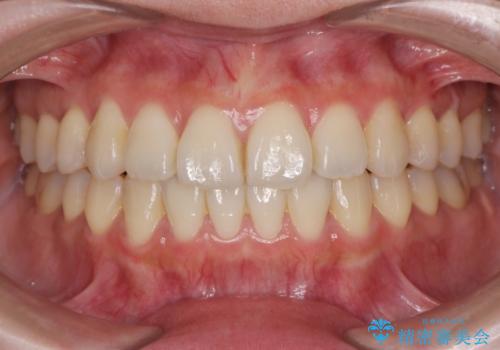

時間はかかりましたが、捻れ、かみ合わせ、前歯の角度の改善が達成され満足いただくことができました。

捻れた奥歯 突き出た前歯を治したい

- 出っ歯に見える前歯、捻れてしまった小臼歯の改善を求めて来院されました。